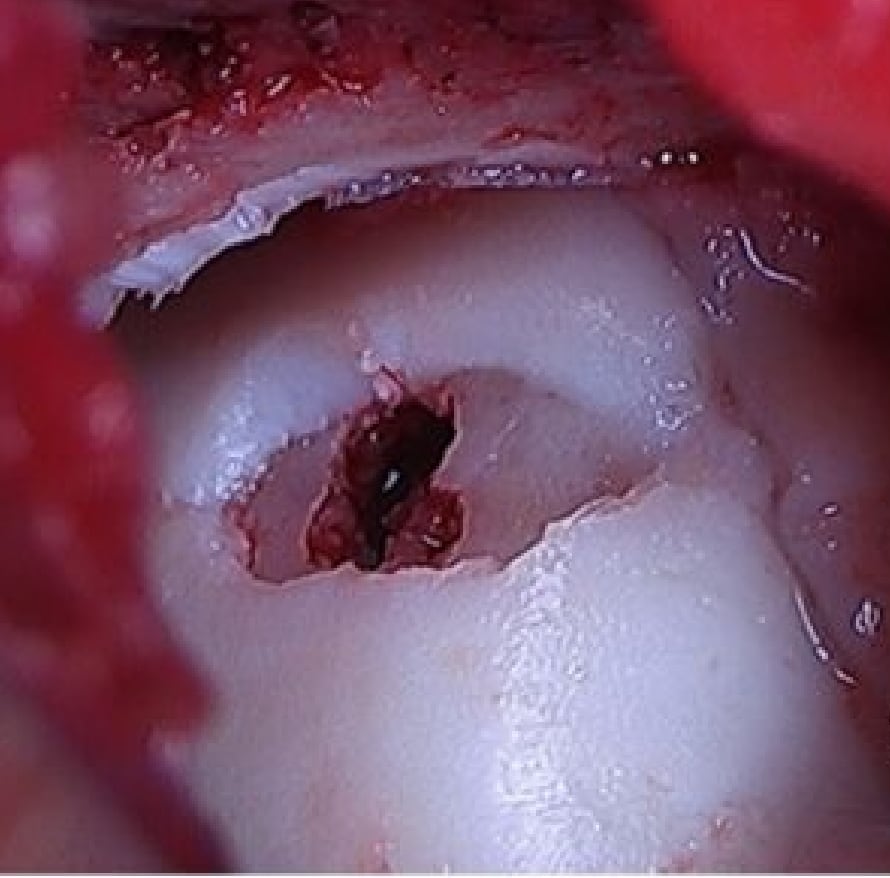

軟骨とその下の骨が剥がれてきて痛みが出る。

⇒骨穿孔/骨軟骨片固定/骨軟骨柱移植

患部の状態により最適な治療方法を選択します。

距骨骨軟骨損傷のCT画像

骨軟骨柱移植前